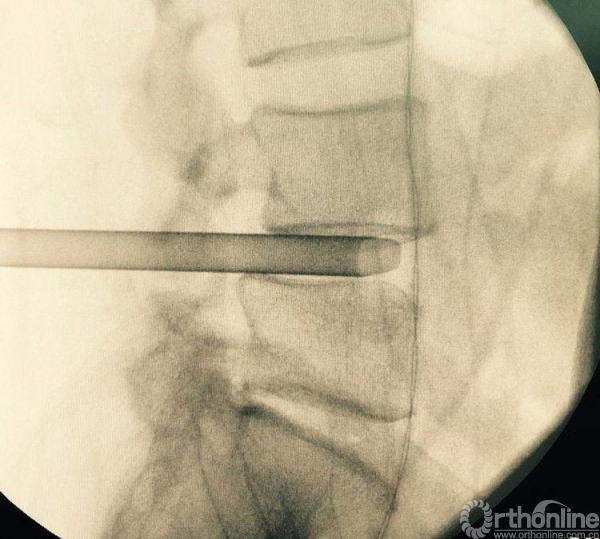

消毒前,给予椎间隙定位

按照定位标志,画出L4-L5椎弓根位置,为零透视下椎管减压做准备

术前透视标记出棘突椎板关节突关节、椎弓根、横突复合体螺钉进钉路线的正位透视片

放入减压工作通道

处理干净椎间隙后,透视观察工作通道的位置,镜下看到前纵韧带的纤维交错位置,为减压充分标志

正位观察透视,判断是否处理至边缘